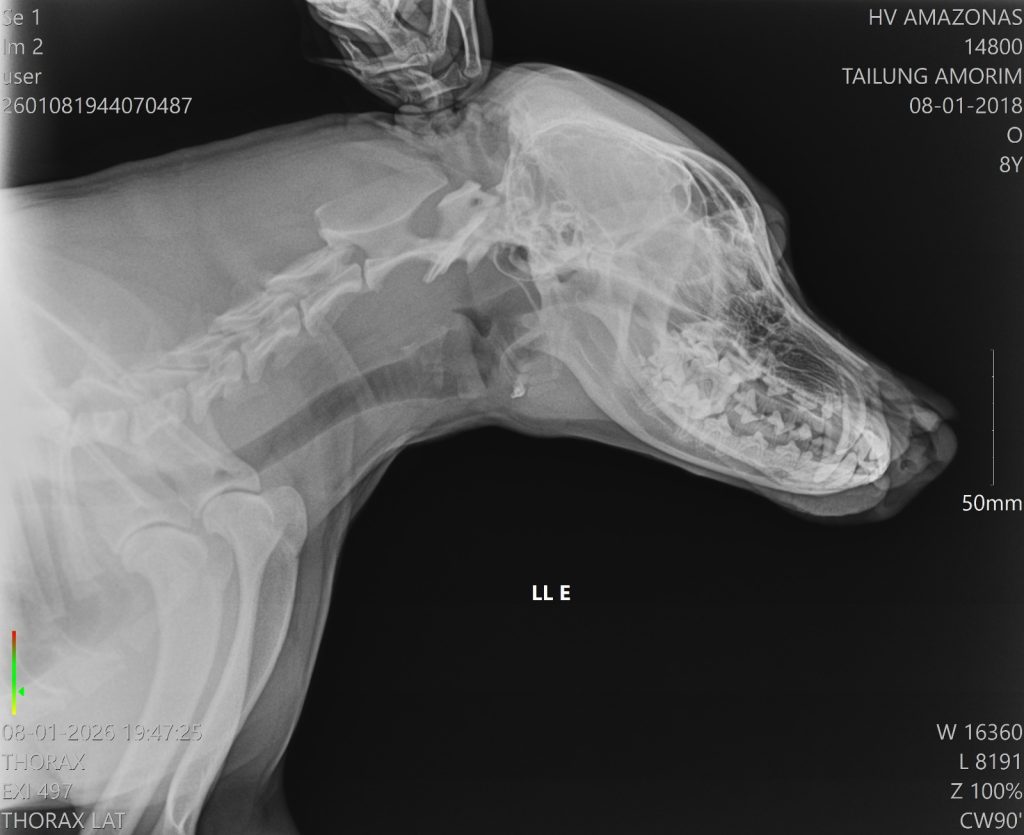

O animal apresentava uma lesão profunda na região do focinho, que foi partido ao meio

A Secretaria de Estado de Proteção Animal (Sepet) socorreu, na noite de quinta-feira (8/01), um cachorro vítima de agressão na comunidade Nossa Senhora do Livramento, localizada no igarapé do Tarumã-Mirim, à margem esquerda do Baixo Rio Negro, zona oeste de Manaus. O animal sofreu um golpe de terçado no focinho e foi encaminhado para atendimento no Hospital Público Veterinário do Amazonas (HPVet-AM).

Após ser vítima de maus-tratos, o animal foi levado pelo tutor de forma segura até a unidade hospitalar. No local, recebeu atendimento de médicos-veterinários, passou por avaliação clínica e está em tratamento intensivo para a recuperação do ferimento.

De acordo com a equipe hospitalar, o cachorro apresentava uma lesão profunda na região do focinho, mas estava consciente e respondeu bem ao atendimento. A cirurgia foi bem-sucedida e o animal já foi encaminhado para casa, onde permanecerá em observação pelo tutor, além de seguir acompanhado pela equipe multidisciplinar do HPVet-AM.